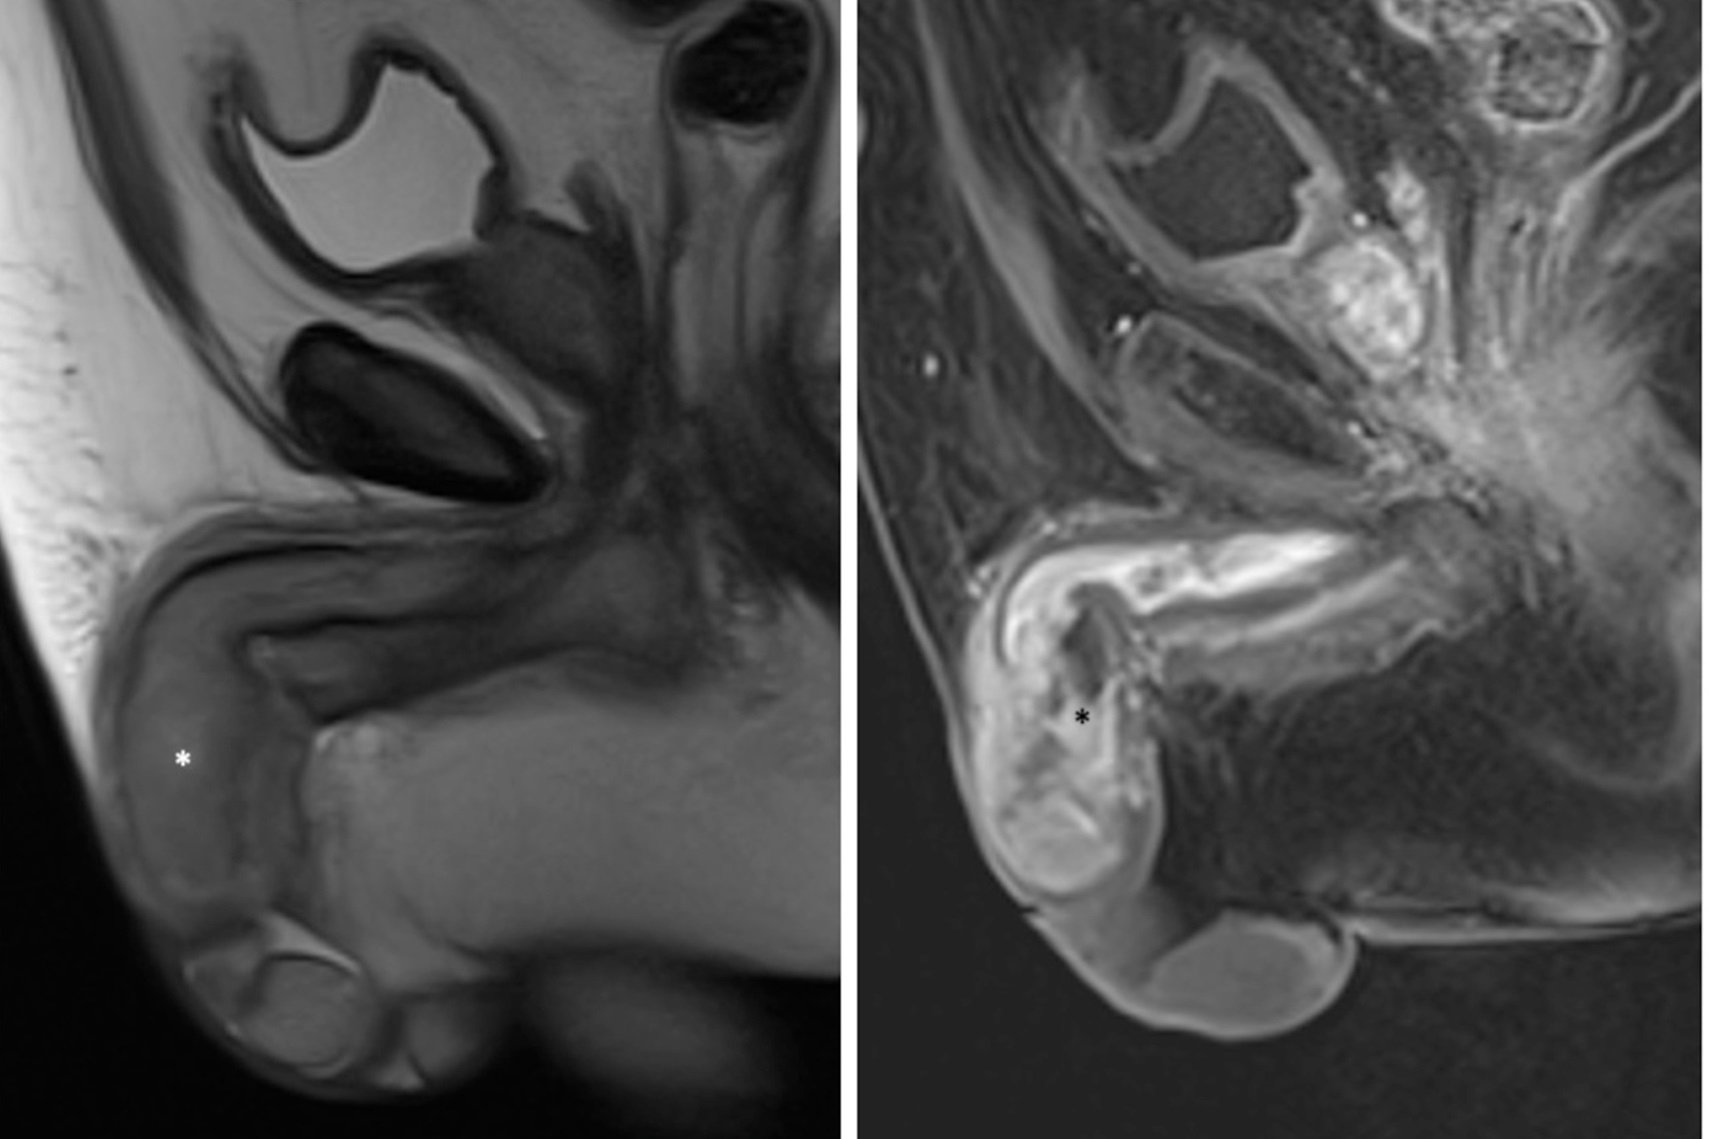

Apesar de raro, o câncer de pênis foi responsável por mais de 6 mil amputações nos últimos 10 anos no Brasil. De acordo com o Ministério da Saúde, o país registrou mais de 21 mil casos da doença entre 2012 e 2022 e mais de 4 mil mortes entre 2011 e 2021.

É possível prevenir o tumor de forma simples, com água e sabão. Mas, além da higiene inadequada, a doença também está relacionada à infecção pelo HPV e à não remoção do prepúcio quando ele não pode ser completamente puxado para trás para expor a glande a fim de higienizá-la.

“O Brasil está na relação dos países com maior incidência de câncer de pênis. E uma das razões para isso é a falta de informação da população da sua existência, do diagnóstico tardio e de que dá para evitar a grande maioria dos casos com água, sabão e vacinação”, destaca o presidente da Sociedade Brasileira de Urologia (SBU), Luiz Otavio Torres.

O câncer de pênis é mais incidente em homens a partir dos 50 anos, mas também pode atingir os mais jovens. Entre os fatores de risco estão: